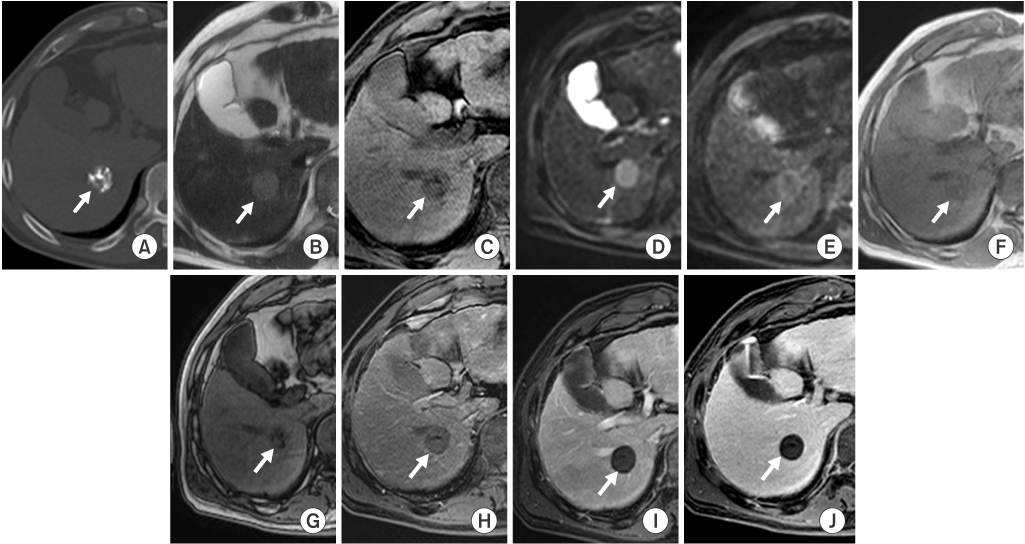

HCCs were analyzed according to the amount of lipiodol uptake on precontrast CT images with bone window setting and were divided into two groups. Group A included 16 HCCs with dense uptake of lipiodol (more than 90%), and group B included 12 HCCs with partial uptake of lipiodol (between 50% and 90%) (Fig. 1). The HCCs which uptook lipiodol less than 50% will be have fewer effect of lipiodol on MR SI, therefore we only included the HCCs showing dense (>90%) and partial (>50%) uptake of lipiodol on precontrast CT images.

Fig. 1

Hepatocellular carcinomas with lipiodol uptake on precontrast computed tomography with bone window setting. (A) The hepatocellular carcinoma (arrow) shows dense uptake of lipiodol in more than 90% of the area of the lesion in hepatic segment 6 and is classified into group A. (B) The hepatocellular carcinoma (arrow) reveals partial uptake of lipiodol in 50% to 90% of the area of the lesion in hepatic segment 5 and is classified into group B.

Fig. 1 Hepatocellular carcinomas with lipiodol uptake on precontrast computed tomography with bone window setting. (A) The hepatocellular carcinoma (arrow) shows dense uptake of lipiodol in more than 90% of the area of the lesion in hepatic segment 6 and is classified into group A. (B) The hepatocellular carcinoma (arrow) reveals partial uptake of lipiodol in 50% to 90% of the area of the lesion in hepatic segment 5 and is classified into group B.